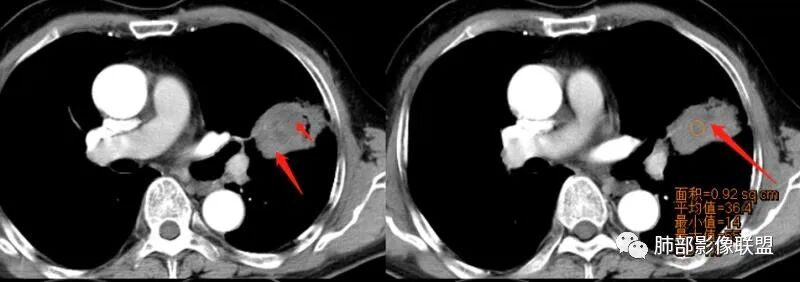

强化如何?

生来征服~浪子:

强化有疑问,前面感觉有低密度的,有些图好像又均匀

小锁:

不均匀中度强化

尘缘:

不均匀轻中度渐进强化。

这个空洞的性质很重要,对最后诊断结果影响大,如果中间没有曲菌球,那就是偏心空洞,指向恶性,如果是曲菌球引起的新月形改变,那就不一定。至于到底是曲菌球还是偏心空洞,需要仔细看看强化情况。

不均匀性强化,远端坏死比较明显

如果强化明确,那就可以排除曲菌球。

2、偏心空腔病灶,气腔略呈新月形,壁不规则,腔内结节相对密实,明显强化且不均,支持新生物而非曲菌球等。炎性空洞多有强化环。

3、病变强化较明显,其内隐约显示多发小斑片状无强化灶,可疑边界不清小灶坏死区。病灶内血管影浅淡、模糊不规则。